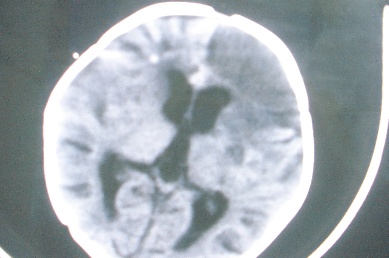

以下是引用余辉在2007-4-30 16:36:00的发言:[br]呵呵,图片不行啊,双肺弥漫斑片状影。右肺门增大,结构模糊。左侧脑室前部室管膜下可见团块状高密度影,周围有低密度环带,左额叶呈大片状低密度改变,略呈楔形,累及灰白质,局部脑沟裂消失,右额叶脑白质亦可见点状病灶(不知是伪影还是真病灶)脑室系统明显扩张,有全脑脑萎缩征象,不知其病史,暂考虑1双肺结核,左额叶结核性脑炎,(左侧脑室前部室管膜下肉芽?出血?)合并脑积水脑萎缩(左额叶低密度区不排除脑梗塞改变)2双肺非特异性炎症合并化脓性脑炎